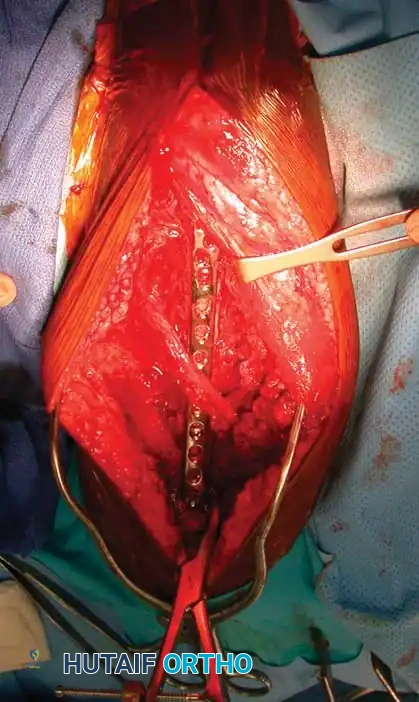

6. Fracture Reduction and Fixation:

* Reflect the entire triceps muscle mass medially to expose the posterior humeral shaft.

* Reduce the fracture and apply the pre-selected LC-DCP. Ensure the radial nerve is completely free and not tethered beneath the plate.

Fig. 54-28 Anterior plating of humeral shaft fracture with limited-contact dynamic compression plate.

For fractures located at the distal metaphyseal-diaphyseal transition zone, standard straight plates may not provide adequate distal purchase. In these scenarios, dual 3.5-mm LC-DCPs or anatomically pre-contoured extra-articular distal humerus plates are required.

Fig. 54-29 Dual plating of distal metaphyseal-diaphyseal humeral shaft fracture.